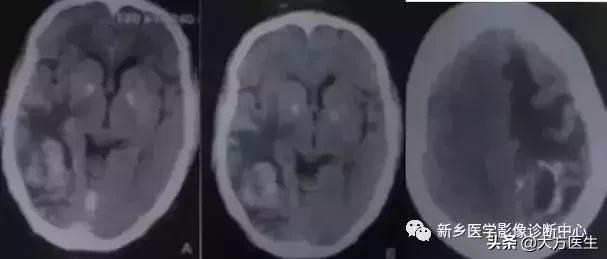

8、囊虫

常有生食猪肉史,癫痫、颅高压,皮下肌肉也可见囊虫结节。

多发钙化型:脑实质内多发小圆形钙化,无强化,囊性病变,壁 上有结节,长T1长T2信号。脑室型:多为脑室形状异常或局限性扩大。